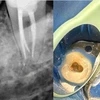

تسوس الأسنان

أمراض الأسنان واللثة